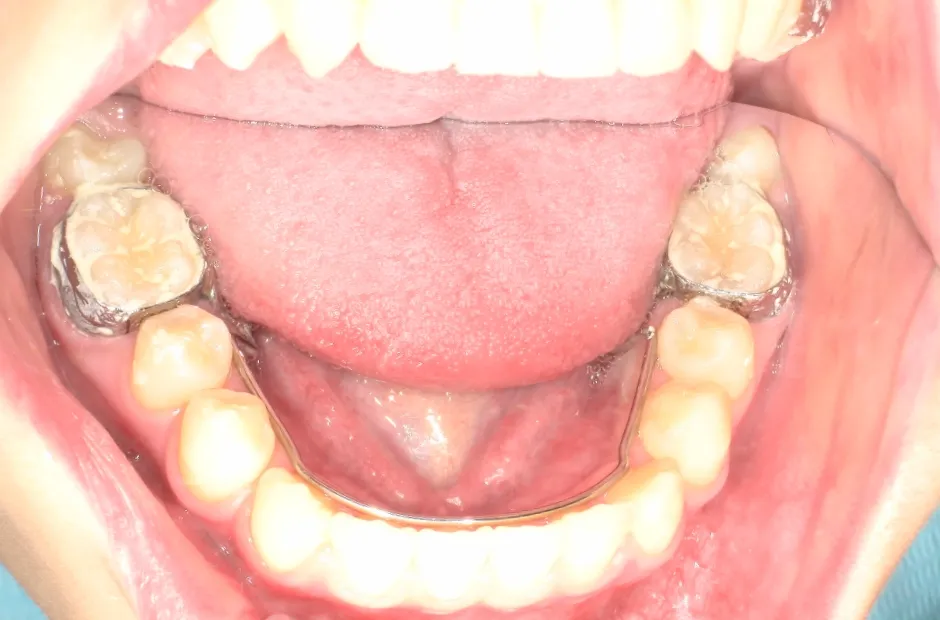

リンガルアーチ

反対咬合

| 診断名・主訴 | 反対咬合 |

|---|---|

| 年齢・性別 | 14歳・女性 |

| 治療期間・回数 | 2年6か月 |

| 治療に用いた主な装置 | リンガル |

| 抜歯部位 | 上顎5,5 下顎4,4 |

| 治療費 | 100万円(税抜) |

| リスク・副作用 | 装置による違和感・疼痛・歯肉退縮・歯根吸収・虫歯のリスクなど |

| 治療に用いた主な装置 | リンガルアーチ(前方誘導弾線) |

| 抜歯部位 | なし |

| 治療費 | 35万円(税抜) |

治療前